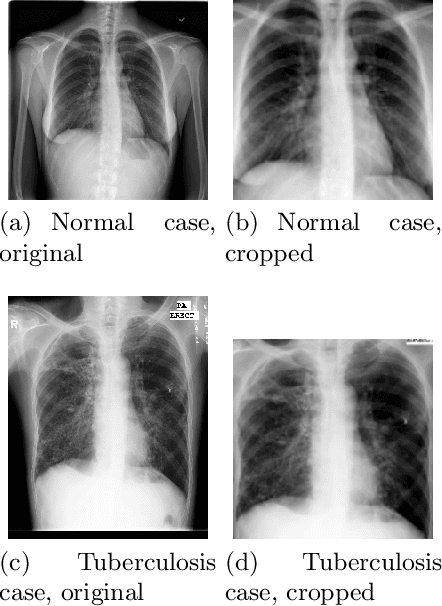

Abstract:Tuberculosis persists as a global health crisis, especially in resource-limited populations and remote regions, with more than 10 million individuals newly infected annually. It stands as a stark symbol of inequity in public health. Tuberculosis impacts roughly a quarter of the global populace, with the majority of cases concentrated in eight countries, accounting for two-thirds of all tuberculosis infections. Although a severe ailment, tuberculosis is both curable and manageable. However, early detection and screening of at-risk populations are imperative. Chest x-ray stands as the predominant imaging technique utilized in tuberculosis screening efforts. However, x-ray screening necessitates skilled radiologists, a resource often scarce, particularly in remote regions with limited resources. Consequently, there is a pressing need for artificial intelligence (AI)-powered systems to support clinicians and healthcare providers in swift screening. However, training a reliable AI model necessitates large-scale high-quality data, which can be difficult and costly to acquire. Inspired by these challenges, in this work, we introduce an explainable self-supervised self-train learning network tailored for tuberculosis case screening. The network achieves an outstanding overall accuracy of 98.14% and demonstrates high recall and precision rates of 95.72% and 99.44%, respectively, in identifying tuberculosis cases, effectively capturing clinically significant features.